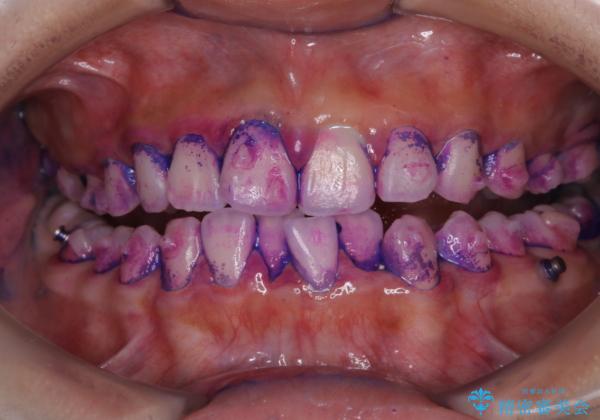

しかし、プラークは歯の色と似ているため、見ただけでは付着しているかどうかがハッキリとは分かりません。

染め出し液を使ってプラークを染め出すことにより、普段の歯みがきで磨き残している場所を目で確かめることができます。

日々の歯磨きを上達するには、まずどこが磨けていないか認識することが大切です。